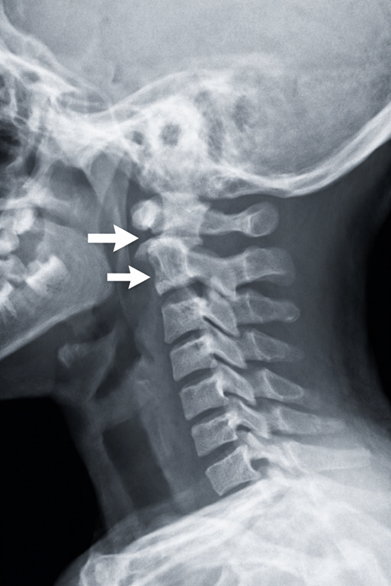

Das KISS-Syndrom (Kopfgelenk-induzierte-Symmetrie-Störung) beschreibt eine funktionelle Störung im Säuglingsalter, bei der es infolge von Belastungen der oberen Kopfgelenke zu asymmetrischen Haltungs- und Bewegungsmustern kommt. Diese Muster sind nicht als reine Fehlhaltung zu verstehen, sondern als Schmerzvermeidungs- und Schonreaktionen. In Verbindung mit nicht integrierten frühkindlichen Reflexen kann sich daraus eine dauerhaft veränderte sensomotorische Organisation entwickeln.